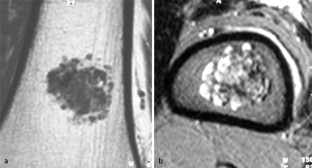

MRI morphology of bone tumors and tumor-like lesions

Für das Staging und die Charakterisierung von Knochentumoren und tumorähnlichen Läsionen ist in der Magnetresonanztomographie (MRT) der Einsatz von Spinechosequenzen erforderlich. Die MRT hat nur einen geringen Stellenwert in der Bestimmung der Dignität. Obwohl viele Knochentumoren und tumorähnliche Läsionen eine vergleichbare Morphologie in dieser bildgebenden Modalität aufweisen, können einige Tumorentitäten mittels MRT recht zuverlässig diagnostiziert werden. Hierzu zählen Knorpeltumoren, die solitäre und aneurysmatische Knochenzyste, der Riesenzelltumor, fetthaltige Läsionen und bis zu einem gewissen Grad auch das Osteoidosteom und das Osteoblastom. Es werden praktische Tipps gegeben, wann bei Tumorverdacht die MRT eingesetzt werden sollte, wie bei einem zufällig bei einer MRT gefundenen Tumor die Untersuchung modifiziert werden sollte und welcher Tumor vorliegen könnte.

Spin-echo sequences are mandatory at MRI for staging and characterization of bone tumors and tumor-like lesions. MRI is of minor value in the estimation of the malignant potential of an osseous lesion. Although many bone tumors and tumor-like lesions present similar morphology at MRI, some entities can be diagnosed with good reliability. These include chondrogenic tumors, solitary and aneurysmal bone cysts, giant cell tumors, lesions containing fatty tissue and, to a certain extent, osteoid-osteomas and osteoblastomas. Practical advice is given regarding when to perform a MRI study in cases of tumor suspicion. Further advices are given for cases a tumor is found incidentally at a MRI study, how to modify the study and which kind of tumor may be present.